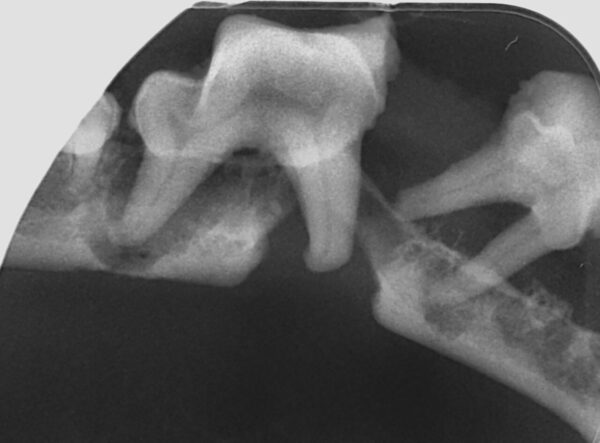

Fracturas dentales

Las radiografías son esenciales en la detección y evaluación de las fracturas del hueso (alveolar, maxilar y mandibular) y del diente (tanto a nivel de la corona, para ver su relación con la pulpa, como de la raíz dental). Los dientes rotos o fracturados son un problema muy común en la práctica veterinaria.

El tratamiento, a menudo, depende de qué partes del diente estén afectadas, raíz y/o corona, y en el caso de esta última, de qué capa(s): esmalte, dentina y si hay exposición o no de la pulpa:

- Las fracturas que no afectan directamente el sistema del conducto radicular se denominan fracturas de corona no complicadas, aunque hay que tener en cuenta que la exposición de los túbulos dentinarios de la dentina puede actuar como vía de entrada de gérmenes y también originar las alteraciones endodónticas (imagen 20).

- Las fracturas que exponen el canal radicular se denominan fracturas complicadas y estos dientes con exposición directa de la pulpa deben tratarse mediante endodoncia o extracción (imágenes 21 y 22).

Cuando la fractura afecte a la raíz del diente este debe ser extraído (imagen 23).